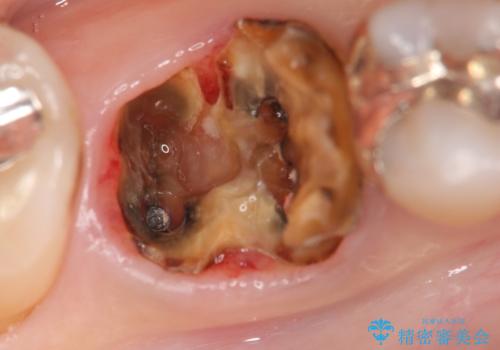

右下の銀歯(右下6)を除去したところ、虫歯が深く保存不可能な状態でした。

ブリッジ、インプラント、入れ歯の3つの選択肢を提案したところ、ブリッジをご希望されました。

抜歯後十分に歯肉の治癒を待ったのち、ブリッジによる補綴治療を行いました。